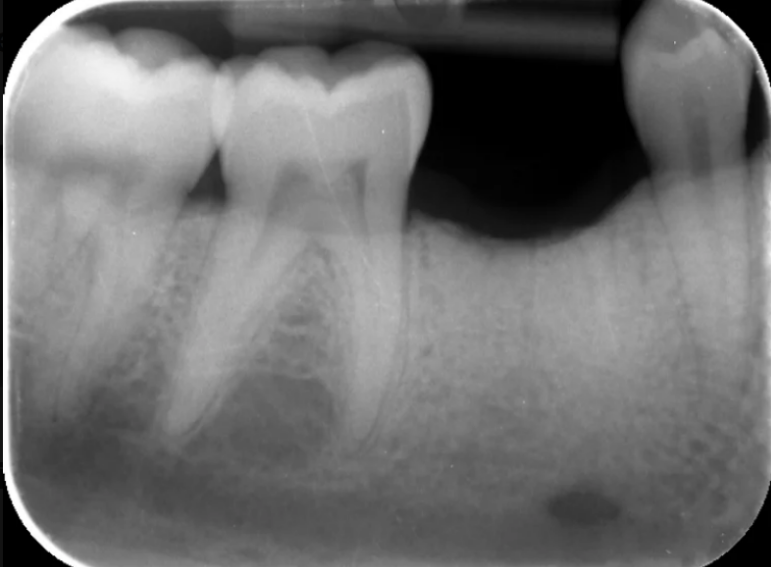

Missing lower premolar due to hypodontia replaced with an implant.